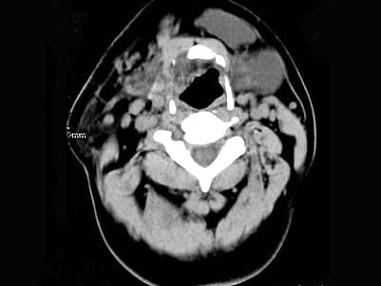

问题 男,32岁,左侧下颌部肿块,CT如图所示,最可能的诊断是 ( )

选项 A、颈部淋巴管瘤 B、舌下腺囊肿 C、颌骨囊肿 D、鳃裂囊肿 E、造釉细胞瘤

答案 B